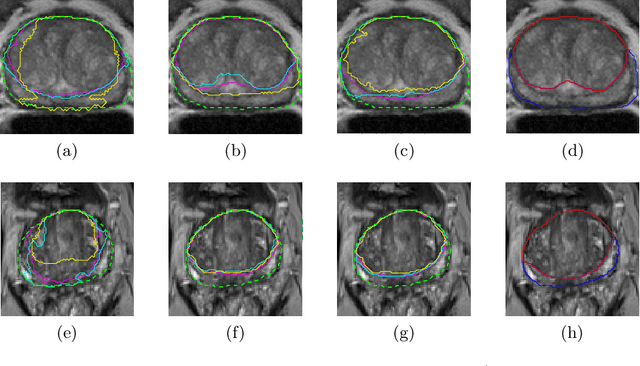

Abstract:Prostate cancer is the most common malignant tumors in men but prostate Magnetic Resonance Imaging (MRI) analysis remains challenging. Besides whole prostate gland segmentation, the capability to differentiate between the blurry boundary of the Central Gland (CG) and Peripheral Zone (PZ) can lead to differential diagnosis, since tumor's frequency and severity differ in these regions. To tackle the prostate zonal segmentation task, we propose a novel Convolutional Neural Network (CNN), called USE-Net, which incorporates Squeeze-and-Excitation (SE) blocks into U-Net. Especially, the SE blocks are added after every Encoder (Enc USE-Net) or Encoder-Decoder block (Enc-Dec USE-Net). This study evaluates the generalization ability of CNN-based architectures on three T2-weighted MRI datasets, each one consisting of a different number of patients and heterogeneous image characteristics, collected by different institutions. The following mixed scheme is used for training/testing: (i) training on either each individual dataset or multiple prostate MRI datasets and (ii) testing on all three datasets with all possible training/testing combinations. USE-Net is compared against three state-of-the-art CNN-based architectures (i.e., U-Net, pix2pix, and Mixed-Scale Dense Network), along with a semi-automatic continuous max-flow model. The results show that training on the union of the datasets generally outperforms training on each dataset separately, allowing for both intra-/cross-dataset generalization. Enc USE-Net shows good overall generalization under any training condition, while Enc-Dec USE-Net remarkably outperforms the other methods when trained on all datasets. These findings reveal that the SE blocks' adaptive feature recalibration provides excellent cross-dataset generalization when testing is performed on samples of the datasets used during training.

Abstract:Prostate cancer is the most common cancer among US men. However, prostate imaging is still challenging despite the advances in multi-parametric Magnetic Resonance Imaging (MRI), which provides both morphologic and functional information pertaining to the pathological regions. Along with whole prostate gland segmentation, distinguishing between the Central Gland (CG) and Peripheral Zone (PZ) can guide towards differential diagnosis, since the frequency and severity of tumors differ in these regions; however, their boundary is often weak and fuzzy. This work presents a preliminary study on Deep Learning to automatically delineate the CG and PZ, aiming at evaluating the generalization ability of Convolutional Neural Networks (CNNs) on two multi-centric MRI prostate datasets. Especially, we compared three CNN-based architectures: SegNet, U-Net, and pix2pix. In such a context, the segmentation performances achieved with/without pre-training were compared in 4-fold cross-validation. In general, U-Net outperforms the other methods, especially when training and testing are performed on multiple datasets.